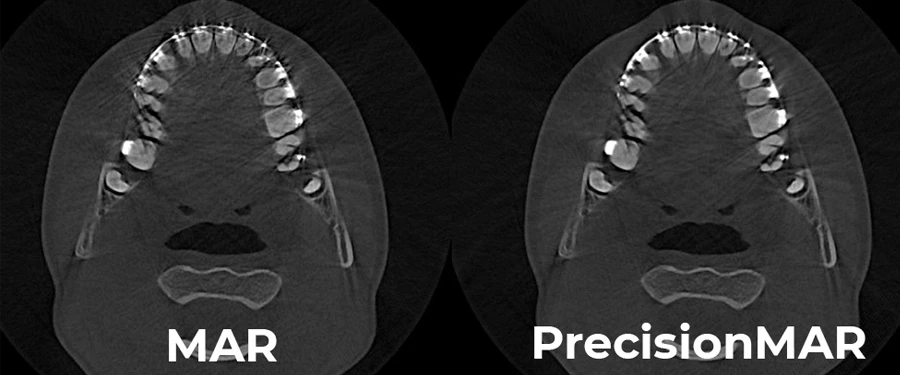

Технология PrecisionMAR™ обеспечивает беспрецедентную четкость при работе с металлами, улучшая качество диагностики и планирование.